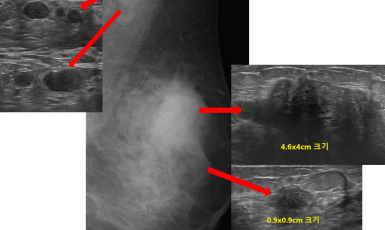

256번째 유방암 진단사례 (2019년6월1일) 1년전부터 왼쪽 가슴에 멍울이 만져지고 통증도 있었으나 그냥 지내다 최근들어 증상이 점점 심해지는 양상보여 진료위해 저희 ..

작성자 레이디유 작성일 06-28 조회 9